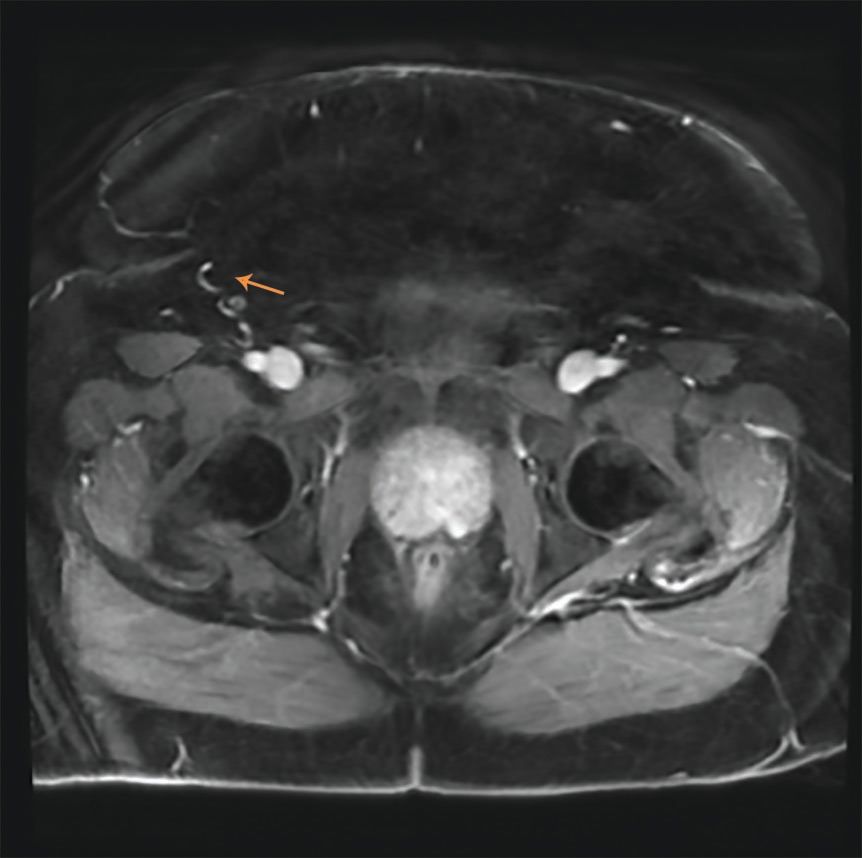

FIGURE 1: Axial T2 weighted image showing the 0.8x0.8 cm lesion (arrow).

An MRI was obtained which found a 0.8 x 0.8 cm lesion in the left medial posterior peripheral zone of the prostate, consistent with the location of the positive core biopsy. (Figure 1) There was focal bulging of the capsule overlying the lesion without evidence of definite extension. It had a circumscribed, homogenous appearance on T2 weighted image. The CT chest showed stable pulmonary nodules.